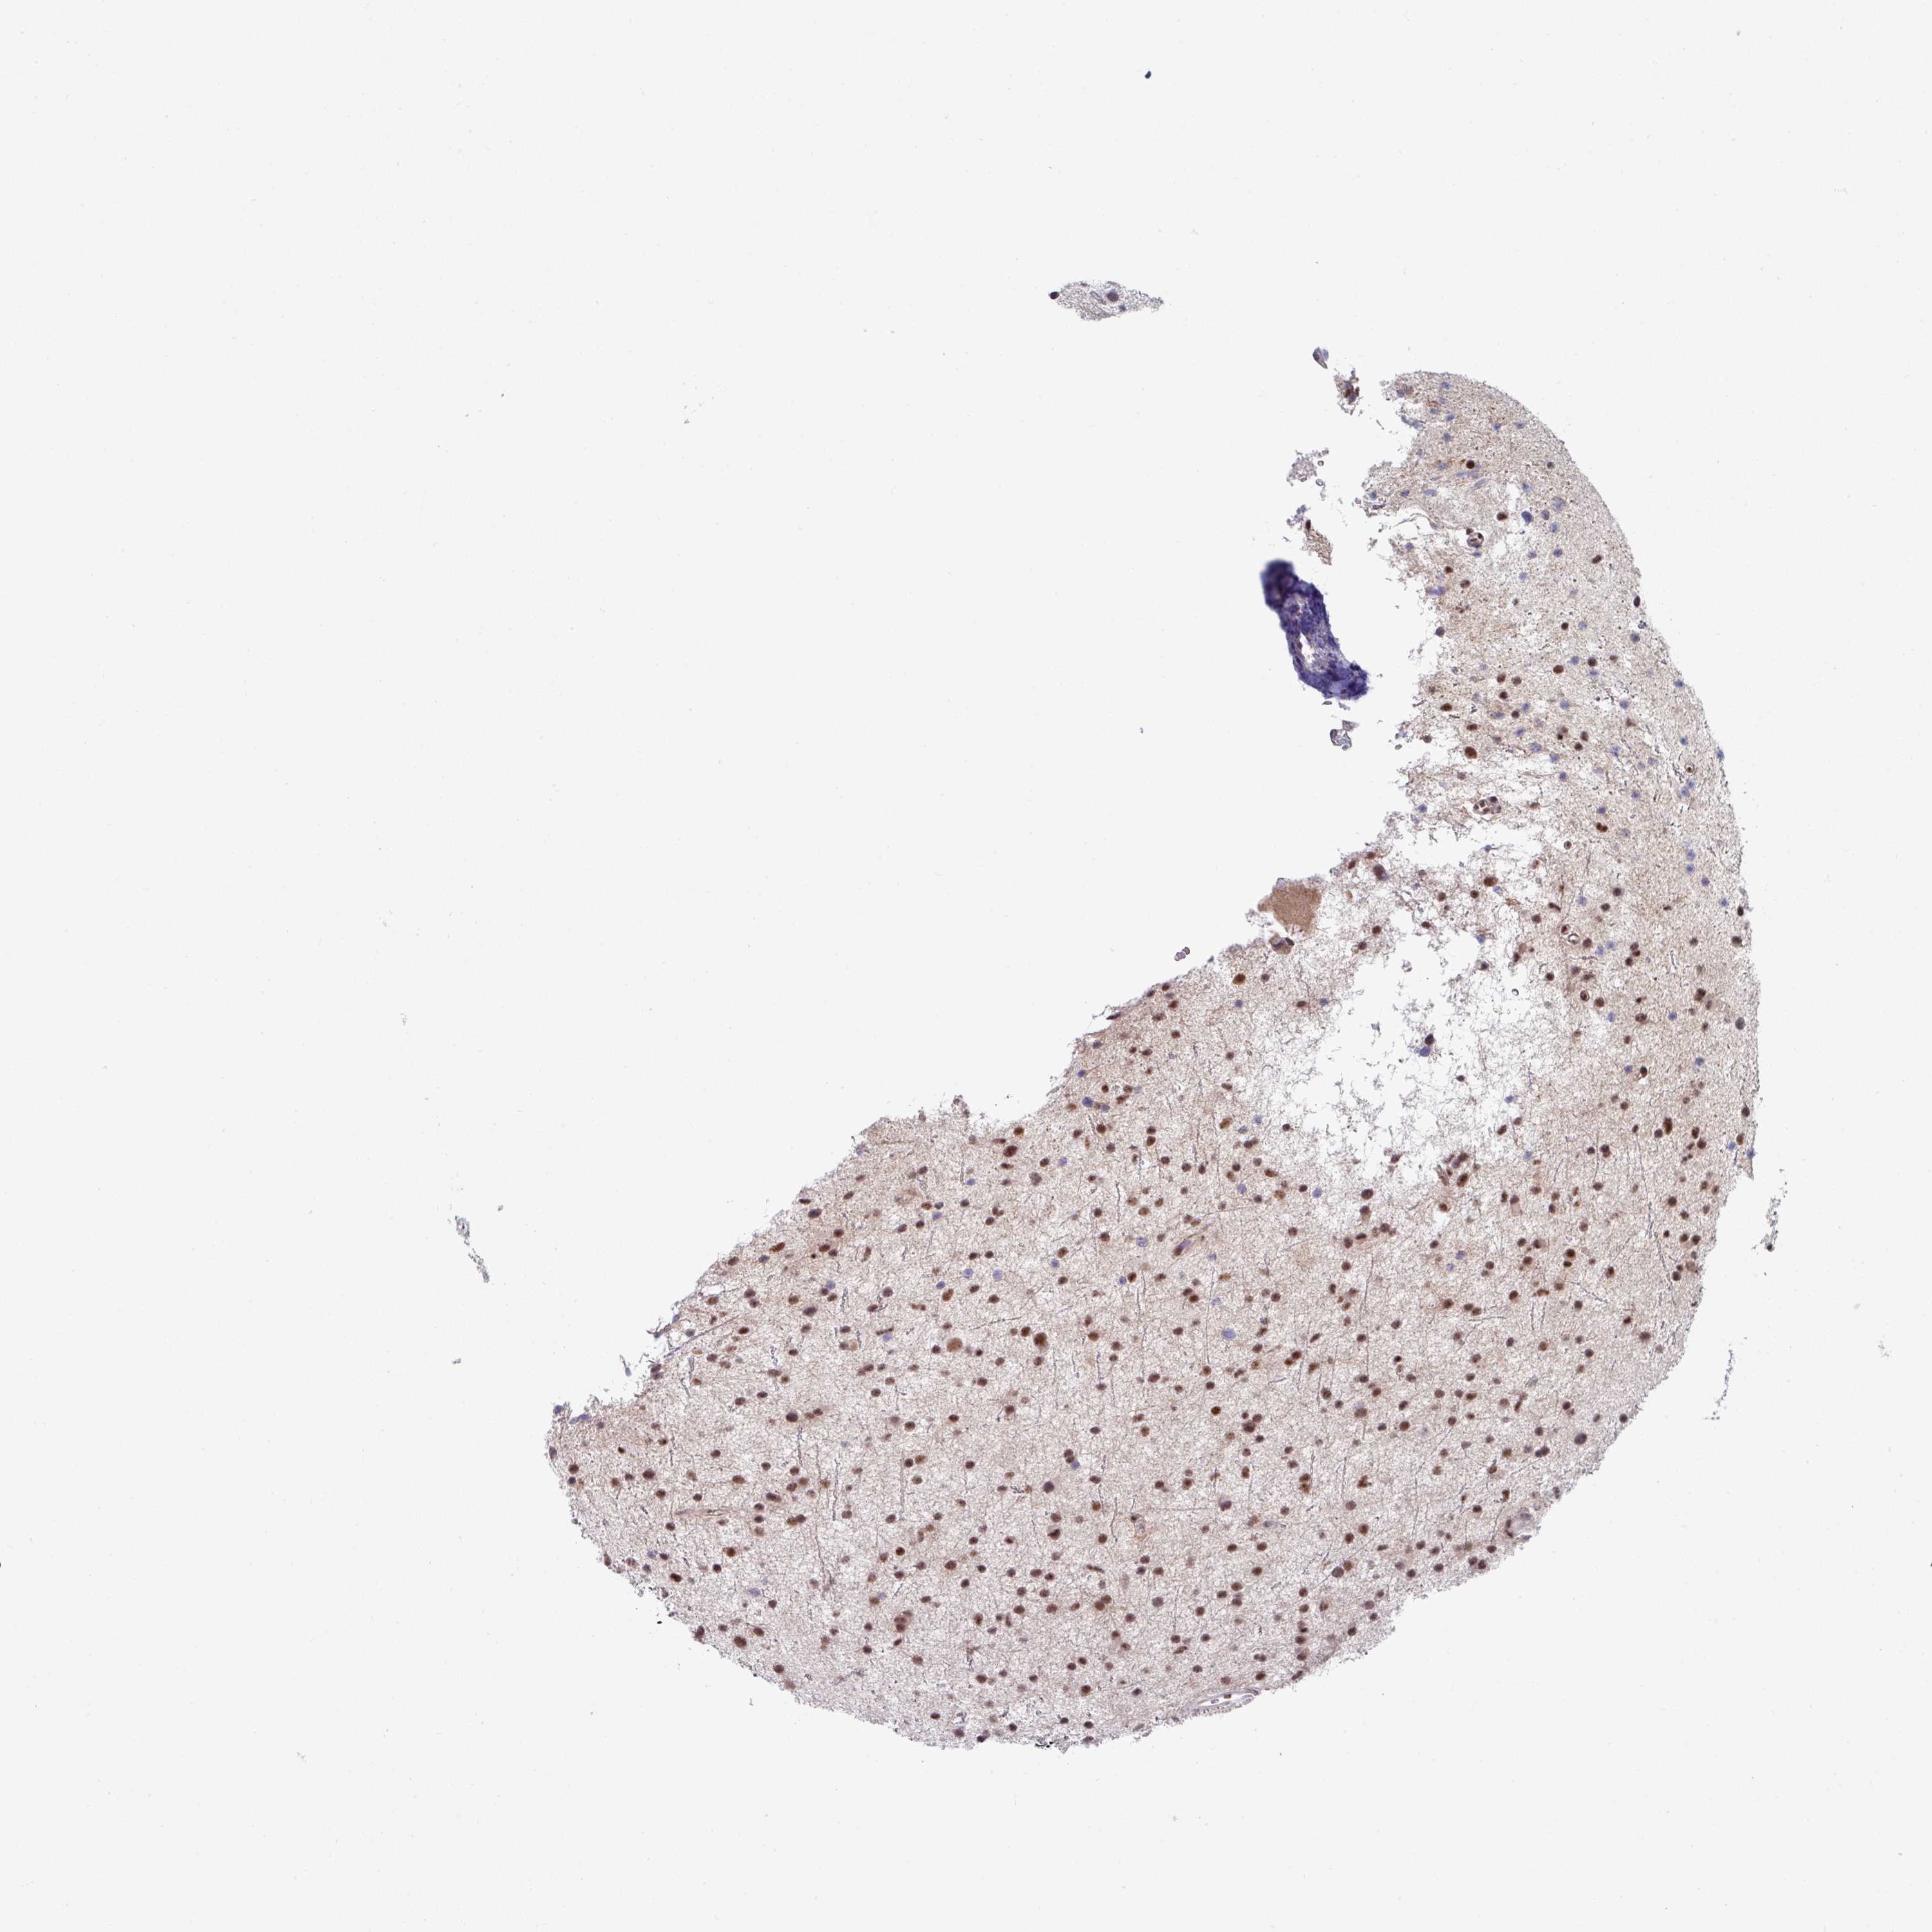

GLIOMA - Protein expressioni

A mouse-over function shows sample information and annotation data. Click on an image to view it in a full screen mode. Samples can be filtered based on level of antibody staining by selecting one or several of the following categories: high, medium, low and not detected. The assay and annotation is described here.

Note that samples used for immunohistochemistry by the Human Protein Atlas do not correspond to samples in the TCGA dataset.

Antibody stainingi

Antibody staining in the annotated cell types in the current human tissue is reported as not detected, low, medium, or high, based on conventional immunohistochemistry profiling in selected tissues. This score is based on the combination of the staining intensity and fraction of stained cells.

Each image is clickable and will lead to virtual microscopy that enables deeper exploration of all samples and also displays staining intensity scores, fraction scores and subcellular localization as well as patient and tissue information for each sample.

Antibody HPA050289

Staining

High

Medium

Low

Not detected

Intensity

Strong

Moderate

Weak

Negative

Quantity

>75%

75%-25%

<25%

None

Location

Nuclear

Cytoplasmic/membranous

Cytoplasmic/membranous,nuclear

Glioma, malignant, High grade

Glioma, malignant, Low grade

Glioblastoma, NOS